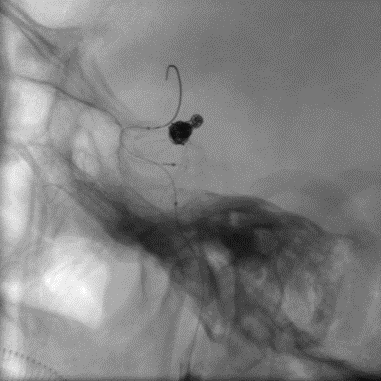

8. 填到瘤颈,这里有一点小Tips:对于这样的案例,我们可以利用微导管或微导丝的弓形来作为弹簧圈的“支撑”,从而进行瘤颈部的处理,这种方法同时保证本就纤细的载瘤动脉的通畅度,而不增加额外操作。事实上,韩国和欧洲原来也有相似技术的文献报道,效果很好。在这里,我们使用确保远端通路的SL10作为支撑导管,Headway 17作为填塞导管,实现了瘤颈部致密填塞。

微导管保护下填塞瘤颈

注:红色箭头为Coiling: Headway 17 Mc,蓝色箭头为Protecting: SL 10 Mc。

微导管/微导丝保护技术

9. 后面的工作就相对轻松了,2.75的Gateway成形后,我们可以看到动脉瘤内弹簧圈已经足够致密,于是撤下弹簧圈微导管,更换为Prowler Plus,释放支架。Enterprise 2顺利释放新的Enterprise的网孔波幅更大,能够在血管外弧充分延展,血管内弧足够压缩,从而获得良好的贴壁性。

球囊扩张-支架释放

扩张前

扩张后

EP2释放